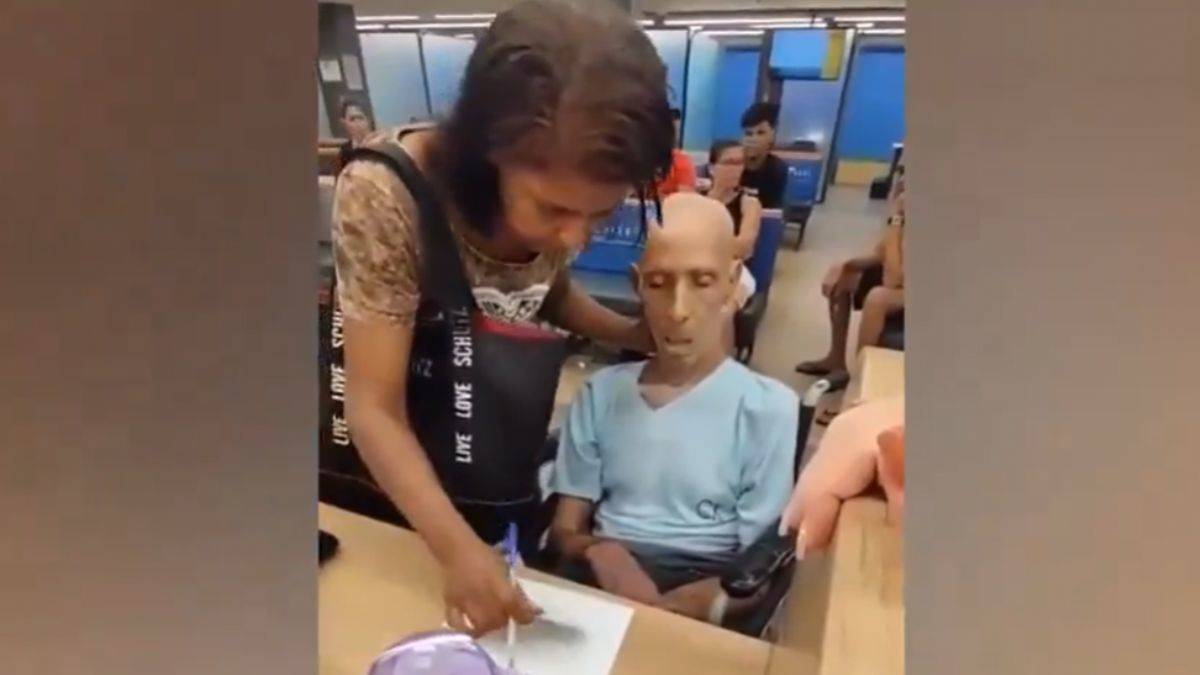

BBC'de yer alan habere göre, sonuçları "The European Heart Journal" dergisinde yayımlanan araştırma, kanser hastalarında kalp ve damar hastalıklarına yakalanma riskinin yüksek olduğunu ortaya koydu.

ABD'nin Penn State Kanser Enstitüsünden araştırmacılar, Amerikalı 3 milyon 230 bin kanser hastasına ait verileri derledikleri meta analizde, hastaların yüzde 38'inin kanser ve ona bağlı komplikasyonlar, yüzde 11'inin ise kalp ve damar rahatsızlıkları nedeniyle yaşamını yitirdiğini belirledi.

Kalp ve damar rahatsızlığı riskinin hastalığın ilk yılında kemoterapi ve radyasyon tedavisinin vücuda verdiği zarar nedeniyle artmasının normal olduğunu ifade eden araştırmacılar, riskin sonraki yıllarda sürdüğüne ve kanser hastalarının nüfusun geneline göre "sürekli yüksek risk altında" olduğuna dikkati çekti.

Mesane, prostat, bağırsak, rahim, göğüs ve gırtlak kanseri hastalarının kalp ve damar rahatsızlıkları riskine en açık gruplar olduğunu belirten araştırmacılar, kanser hastalarının tedavi sürecinde kalp ve damar sağlığı açısından da sürekli gözetim altında tutulması gerektiği uyarısında bulundu.